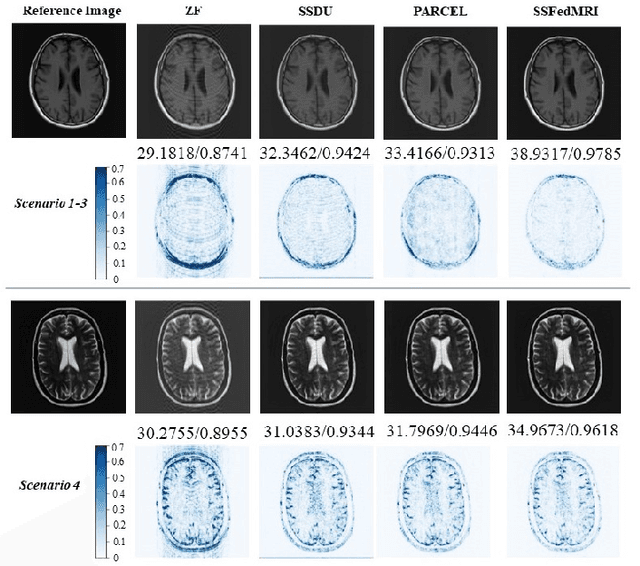

Federated learning (FL) based magnetic resonance (MR) image reconstruction can facilitate learning valuable priors from multi-site institutions without violating patient's privacy for accelerating MR imaging. However, existing methods rely on fully sampled data for collaborative training of the model. The client that only possesses undersampled data can neither participate in FL nor benefit from other clients. Furthermore, heterogeneous data distributions hinder FL from training an effective deep learning reconstruction model and thus cause performance degradation. To address these issues, we propose a Self-Supervised Federated Learning method (SSFedMRI). SSFedMRI explores the physics-based contrastive reconstruction networks in each client to realize cross-site collaborative training in the absence of fully sampled data. Furthermore, a personalized soft update scheme is designed to simultaneously capture the global shared representations among different centers and maintain the specific data distribution of each client. The proposed method is evaluated on four datasets and compared to the latest state-of-the-art approaches. Experimental results demonstrate that SSFedMRI possesses strong capability in reconstructing accurate MR images both visually and quantitatively on both in-distribution and out-of-distribution datasets.